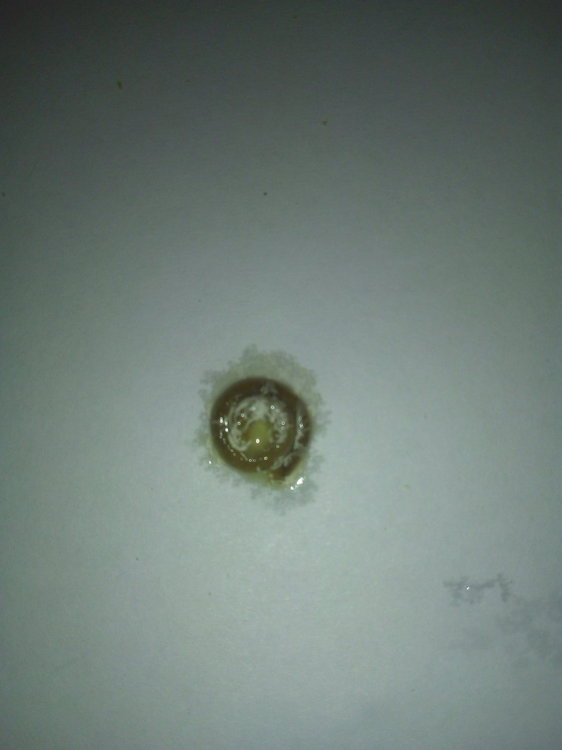

Здравствуйте! Пожалуйста, помогите моему волнистику. Больше месяца назад начались проблемы с калом. Начал какать редко и большими кучками. Сначала не придала значения, а потом у него начался сильнейший запор. Кеша перестал есть, пить, не мог вообще сходить в туалет. Орнитологов у нас нет в городе. После изучения информации на форумах, пропоила его биссептолом суспензией, кормили кашей и поили со шприца. В клюв капала вазелиновое масло. В еду линекс сыпала. Сейчас измельчаю карсил и добавляю в сухой корм. Ему стало легче, кал так и восстановился. Ходит большими кучками. Стал тяжело дышать, плохо и мало летать. На животе появилась опухоль. Сдали анализы на криптоспоридиоз и сальмонеллез- отрицательные. Сделали ренген. По результатам- проблемы с легкими и опухоль. Что делать? Умоляю, помогите!